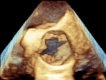

A 24-year-old man with systemic lupus erythematosus and antiphospholipid syndrome complicated by lupus nephritis presented with acute limb ischaemia secondary to an embolus. Following embolectomy, the patient underwent a transthoracic echocardiogram which revealed a large vegetation on all three cusps of the aortic valve. The patient was taken for an urgent aortic valve replacement with a mechanical valve. Cultures of one cusp remained sterile. Histopathological examination of the remaining two cusps revealed sterile fibrin-rich thrombotic vegetations characteristic of non-bacterial thrombotic endocarditis.